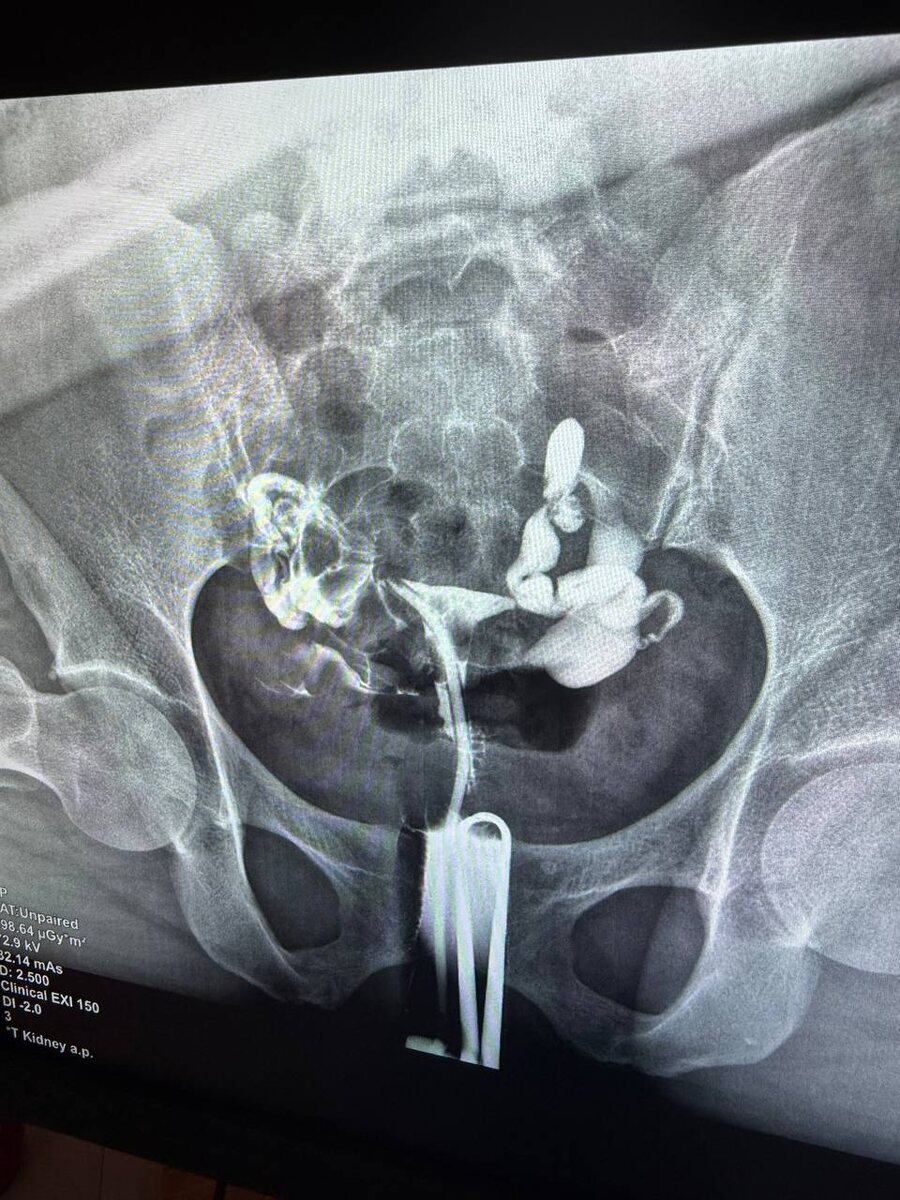

Пациентка 28 лет , в октябре была операция по поводу эндометрроидных кист ( рецидив после первой операции) и выраженный спаечный процесс

Операцию выполняла я , в конце был введен противоспаечный гель в брюшную полость . Сегодня данная пациентка пришла на оценку проходимости маточных труб . Честно - она сама не ожидала , что будут проходимы трубы , и я признаюсь тоже- так как спаечный процесс был тотальный - трубы , яичники , кишечники - всё в спайках ! Но какая была радость когда - справа абсолютно хорошо проходимая труба , слева- увы нет . Но тем не менее, даже с одной проходимой маточной трубой возможна самостоятельная беременность!!! 🤰 и я искренне верю и знаю , что детям быть 🙏🤍 Ваша доктор Замалтдинова РР🌹

Пациентка 28 лет , в октябре была операция по поводу эндометрроидных кист ( рецидив после первой операции) и выраженный спаечный процесс. Операцию выполняла я , в конце был введен противоспаечный гель в брюшную полость . Сегодня данная пациентка пришла на оценку проходимости маточных труб . Честно - она сама не ожидала , что будут проходимы трубы , и я признаюсь тоже- так как спаечный процесс был тотальный - трубы , яичники , кишечники - всё в спайках !

Но какая была радость когда - справа абсолютно хорошо проходимая труба , слева- увы нет . Но тем не менее, даже с одной проходимой маточной трубой возможна самостоятельная беременность!!! 🤰 и я искренне верю и знаю , что детям быть 🙏🤍